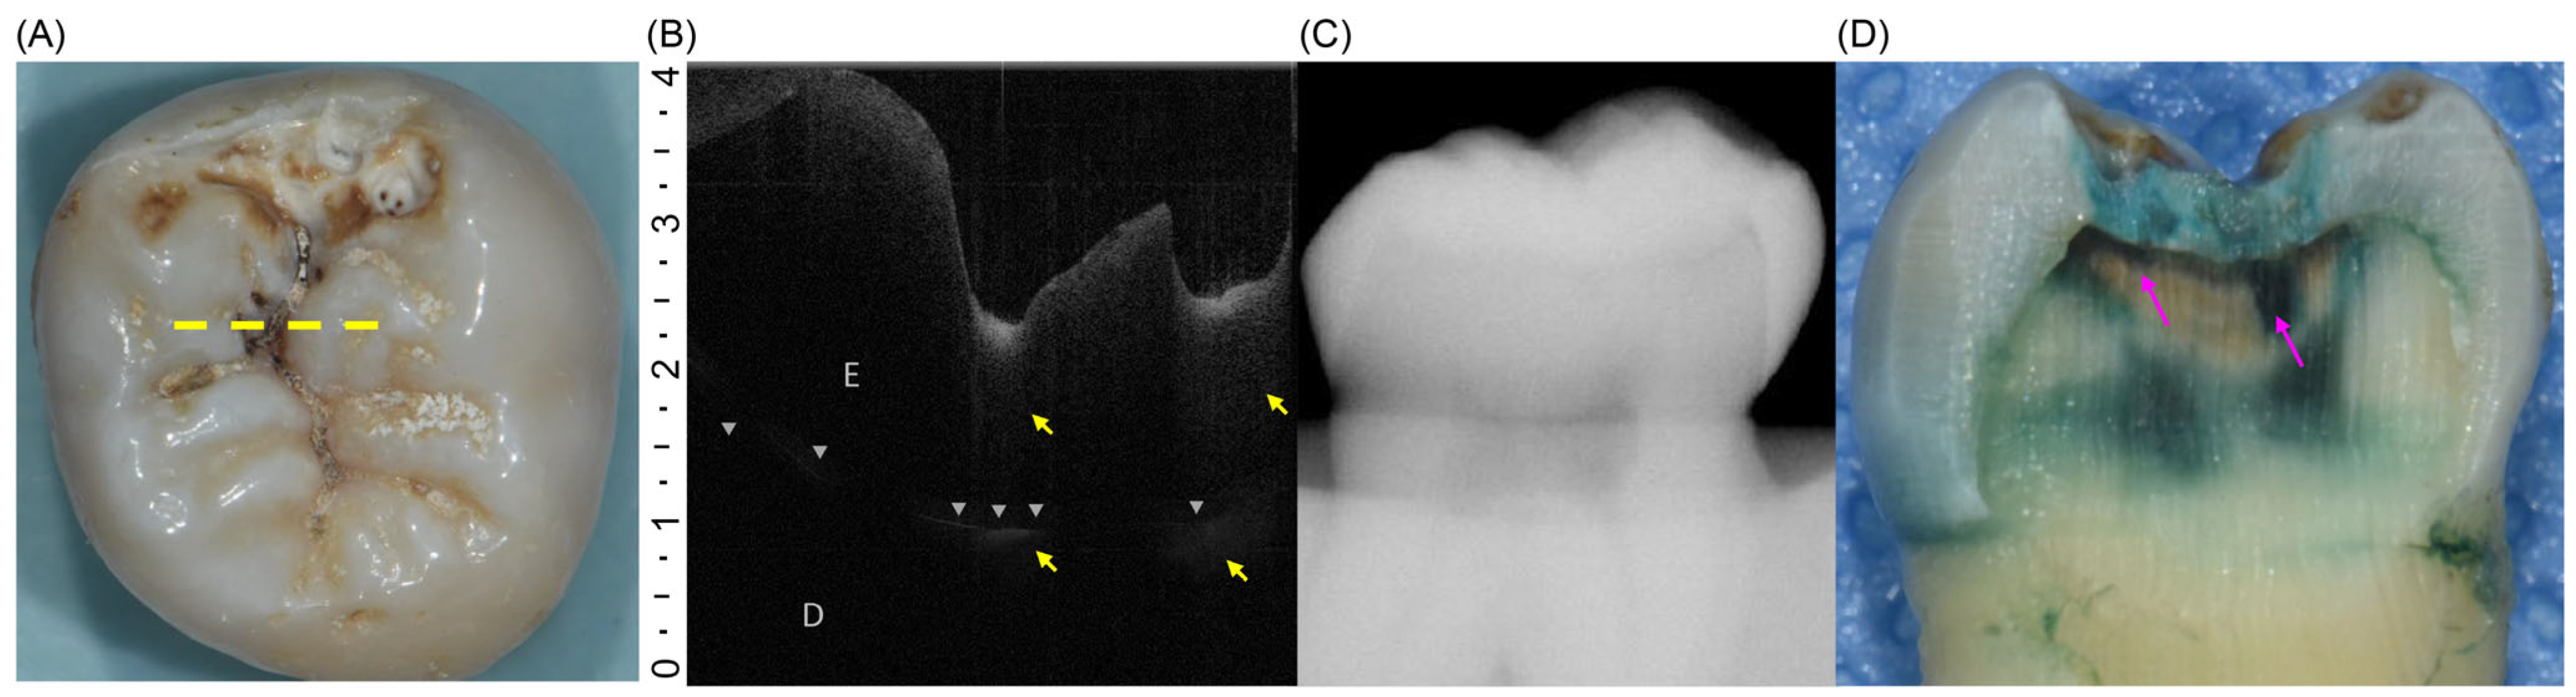

All 110 extracted teeth were assessed using both diagnostic approaches and classified as having initial or moderate lesions (Figure 2A and Figure 3A). However, during the histological reference test, three specimens were lost because of unintended fractures that occurred during sectioning. Consequently, the final analysis included 107 teeth, with the distribution of lesions confirmed by histology, showing 64 teeth with initial lesions and 43 teeth with moderate lesions (Table 2) (Figure 2D and Figure 3D). On OCT, the initial lesions appeared as localized hyperreflective bands confined to the enamel, with an intact DEJ and a continuous surface line (Figure 2B). Moderate lesions showed a broader hyperreflective zone crossing the DEJ with underlying shadowing and surface disruption (Figure 3B). In contrast, intraoral radiographs rarely displayed apparent radiolucency of the initial lesions and frequently showed no discernible change, even for moderate occlusal involvement (Figure 2C and Figure 3C).

Figure 3. (A) Occlusal view of a tooth with a moderate lesion. The yellow dotted line indicates the scan plane for OCT imaging. (B) OCT B-scan showing a surface irregularity and a broad hyperreflective zone (yellow arrows) extending beyond the DEJ (gray triangles) with underlying shadowing in the dentin layer. D, dentin; E, enamel. (C) Intraoral radiograph showing no detectable radiolucency. (D) Sectioned specimens stained with 0.5% acid red solution. The pink arrow indicates demineralized area extending beyond the outer third of the dentin.